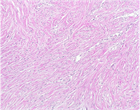

1. 早期の胸膜中皮腫と反応性中皮細胞増生(反応性中皮過形成)の病理像は類似し、良悪の鑑別は慎重に行う必要がある。BAP1免疫染色、CDKN2A遺伝子の中皮腫でのホモ接合性欠失の検出が鑑別に役立つ。